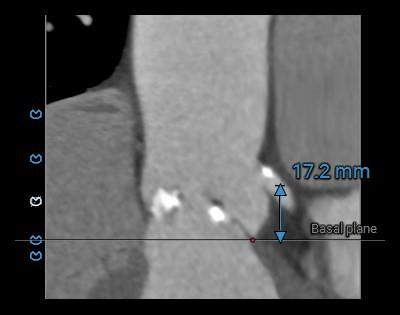

瓣上测量

2.主动脉瓣瓣环周长95.7mm,平均周长径30.5mm。

3.左心室舒张期前后径59mm,术中发生恶性心律失常风险大,预装瓣膜,备自动除颤仪和体外循环。